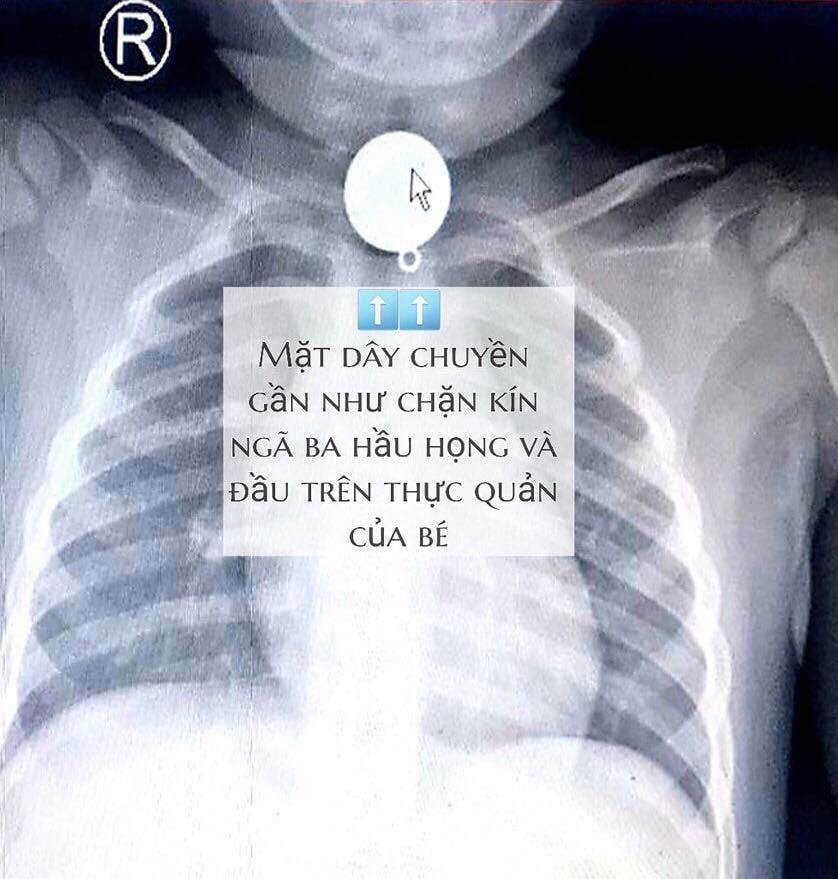

Khi bệnh nhân đến Bệnh viện TƯ Quân đội 108 chụp phim CT- Scan ngực thì phát hiện tổn thương dạng đám mờ tương đối thuần nhất thùy dưới phổi phải (phân thùy 10), có hạch trung thất nên cần chẩn đoán phân biệt giữa viêm phổi và u phổi.

Do mảnh ớt không cản quang gây nên việc khó phát hiện trên phim X quang phổi, chính vì vậy bệnh nhân đi khám nhiều nơi nhưng không phát hiện ra. Tuy nhiên, một thời gian sau miếng ớt gây viêm nhiễm tại chỗ và lan cả vùng phổi xung quanh và khi chụp CT- Scan ngực có tổn thương hạch viêm trung thất kết hợp với đám mờ ở phân thùy 10 bên phải do vậy rất dễ nhầm với tổn thương ung thư phổi.

Bác sĩ Nguyễn Văn Sơn, Khoa Nội hô hấp - Bệnh viện TWQĐ 108 cho biết, mảnh ớt không cản quang gây nên việc khó phát hiện trên phim X quang phổi, chính vì vậy bệnh nhân đi khám nhiều nơi nhưng không phát hiện ra. Một thời gian sau, miếng ớt gây viêm nhiễm tại chỗ và lan cả vùng phổi xung quanh.